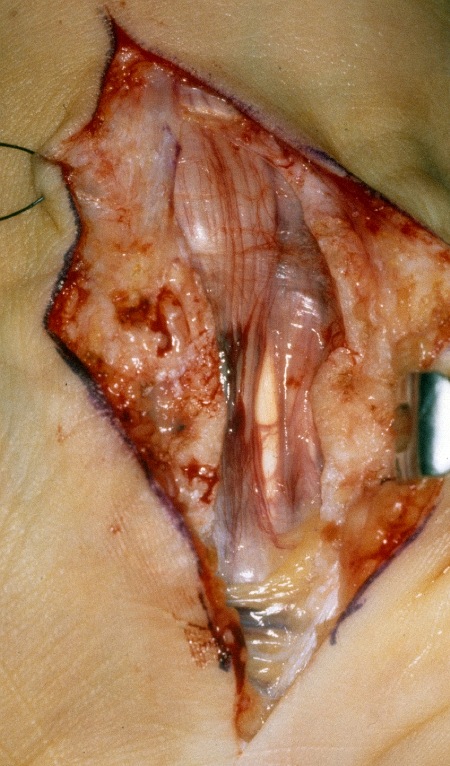

Sanduhrförmig komprimierter N. medianus nach langem Zuwarten und Behandlung bei einem Heilpraktiker

Sanduhrförmig komprimierter N. medianus nach langem Zuwarten und Behandlung bei einem Heilpraktiker